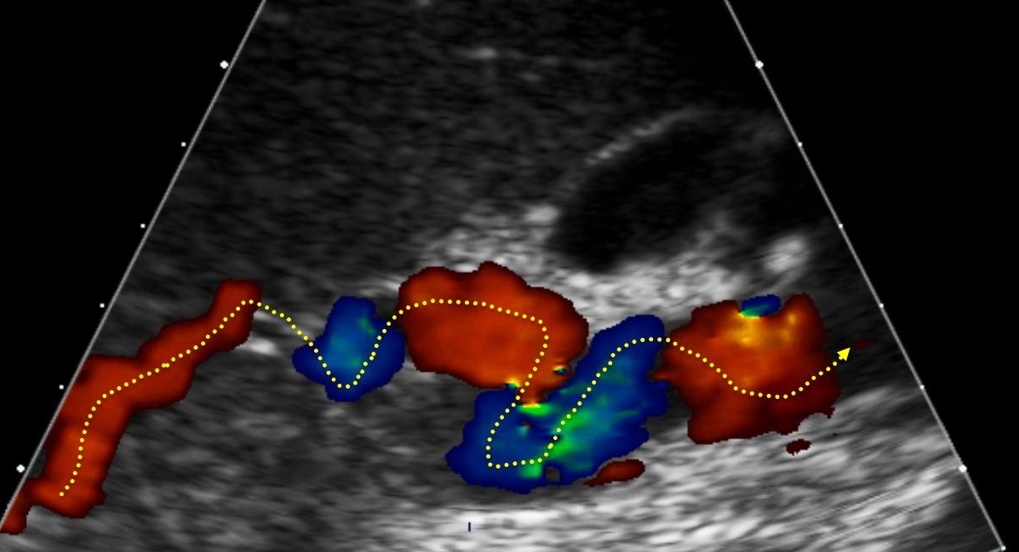

Особенности и диагностика левостороннего кровотока